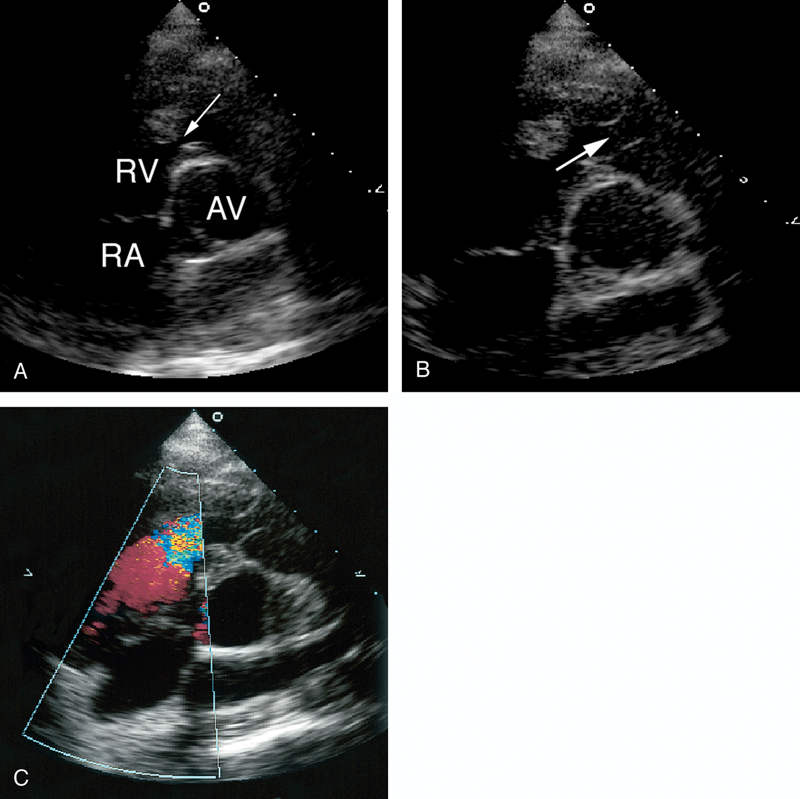

فحوصات تشخيصية لبعض امراض القلب والشرايين التاجية